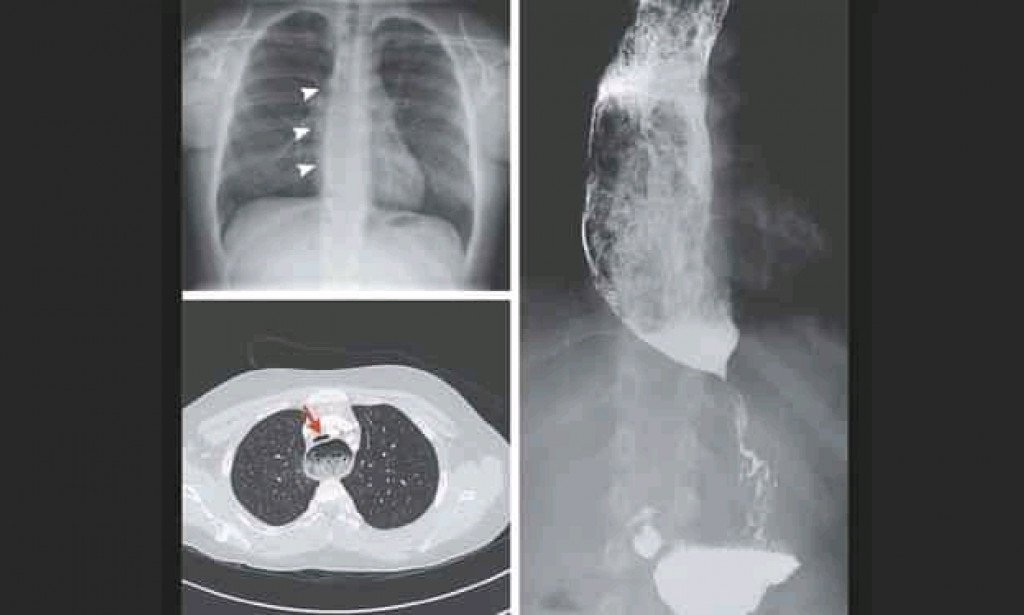

Esophageal aperistalsis and impaired relaxation of the lower esophageal sphincter (LES) during deglutition are symptoms of achalasia, a rare esophageal motility disorder.

Patients with suspected achalasia should have an upper esophagogastroduodenoscopy (EGD) performed to rule out pseudoachalasia caused by an obstructing mass.High-resolution manometry (HRM), the current gold standard test for achalasia diagnosis, is used to confirm the diagnosis.

Achalasia is a heterogeneous condition with three distinct forms based on manometric patterns: type I (classic) with low contractility in the oesophagus body, type II with intermittent panesophageal pressurisation, and type III (spastic) with premature or spastic distal esophageal contractions.